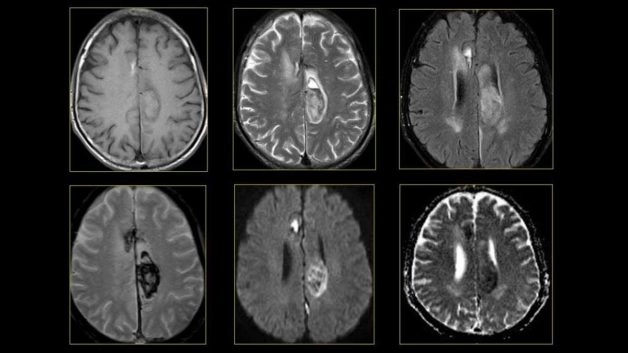

Chụp cộng hưởng từ não bộ là kỹ thuật chẩn đoán hình ảnh tiến tiến, sử dụng từ trường và sóng radio để tạo ra hình ảnh chi tiết của cấu trúc nhu mô não và mạch máu. Khi chụp, sóng radio và từ trường sẽ tác động vào các nguyên tử Hydrogen trong cơ thể phát ra tín hiệu và tín hiệu này được thu nhận lại rồi gửi dữ liệu đến máy tính. Khi dữ liệu được truyền đến máy tính, tín hiệu này sẽ được thu thập và xử lý để cho ra kết quả là những hình ảnh các mặt cắt ngang của não. Hình ảnh này có thể được chuyển đổi thành hình ảnh 3D của não, giúp xác định các dấu hiệu bất thường trong não và các mạch máu.

Với kỹ thuật này, người bệnh không cần tiêm thuốc cản quang vẫn thu được hình ảnh chi tiết và rõ nét về các bất thường của sọ não và các mạch máu. Phương pháp có ưu thế hơn hẳn các phương pháp chẩn đoán hình ảnh khác như chụp cắt lớp vi tính (CLVT), X-quang,… bởi vì không sử dụng bức xạ, không xâm lấn. Chính vì vậy, chụp MRI được áp dụng phổ biến trong việc chẩn đoán các bệnh lý liên quan đến thần kinh và não bộ.

Như đã nói ở trên, chụp MRI não giúp bác sĩ phát hiện và chẩn đoán một số bệnh lý ở não bộ như:

– Chấn thương sọ não

– Viêm màng não, viêm não

– Tai biến mạch máu não, đột quỵ

– Dị dạng mạch máu não

– Xơ cứng rải rác

– Thoái hóa não chất trắng

– Phát hiện các khối u não, u dây thần kinh sọ não

– Một số dị tật bẩm sinh khác như khuyết não, teo não,…

Chụp MRI cho não giúp bác sĩ phát hiện và chẩn đoán một số bệnh lý như chấn thương sọ não, viêm màng não, viêm não,….